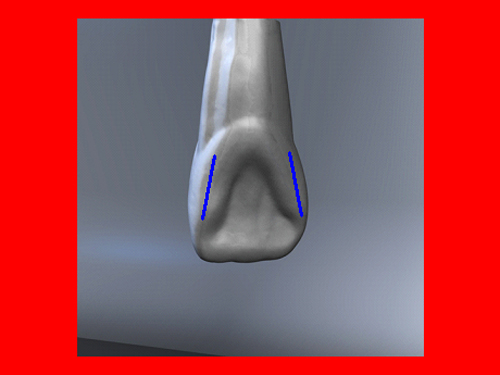

En ciertas áreas del saber humano, el lenguaje confuso o criptográfico Muchas son las técnicas elaboradas para lograr un desgaste selectivo, y numerosos autores han expuesto en su momento variadas formas de lograr una función oclusal fisiológica mediante el ajuste de la misma. Han pasado años desde entonces y, sin embargo, aún hoy, un altísimo porcentaje de profesionales “navega” por el mar de la confusión oclusal, dada la diversidad de conceptos y escuelas, sin lograr arribar a costa alguna donde poder anclar un conocimiento sólido sobre cómo tratar la oclusión Ya se esté realizando una simple obturación, endodoncia, incrustación, radectomía u ortodoncia, la lógica pocas veces, en la mayoría de los casos, vincula un tratamiento con otro, siendo el resultado final el mismo caos inicial; enmascarado por mucho tratamiento profesional. El ajuste oclusal es un medio inicial de proveer al sistema enfermo de: Dicha técnica, que puede ser terapéutica en sí misma; consta de dos etapas, a saber: 1) Ajuste Oclusal por Adición Mediante el estudio de la guía anterior, encargada de efectuar las Disclusiones durante las excursiones mandibulares, podremos observar si ésta es funcional o no. • Marcas de carácter continuo, si en ese recorrido se produce la Disclusión de los sectores posteriores y todo marcha correctamente. FIG 1-2 Si por el contrario observamos: • Marcas de carácter discontinuo, significa que dicha Disclusión se está efectuando por medio de una pieza dentaria posterior a la guía anterior. FIG 3-4-5 (FIGS. 3, 4 Y 5). En la figura 6 las flechas indican, en un caso clínico de análisis oclusal, la presencia de marcas discontinuas que indican Interferencias en Propulsiva. FIG 6-7 Y por último, si existieran: • Abrasiones de las áreas discluyentes en las áreas de diagnóstico de la guía anterior, deberemos aportar material a dicha zona para no permitir el choque lateral de las piezas posteriores (Ajuste Oclusal por Adición) En las imágenes 11 y 12 podemos observar la adición de composite en la punta de un canino derecho, previa la observación de la Faceta Parafuncional remarcada durante el análisis oclusal en el articulador. (FIGS. 8 A 12). 2) Ajuste oclusal por Sustracción o Desgaste Habiendo cumplido ya con la verificación de la funcionalidad de la Guía Anterior, comenzamos los desgastes en céntrica, a fin de lograr un único arco de cierre, guiado eficazmente por la Guía Anterior; es decir: la coincidencia entre Oclusión Habitual y Oclusión en Relación Céntrica. En este caso, intentar gastar dichos puntos, de ser posible sólo en las cúspides de corte o no fundamentales: • Crestas Triangulares Internas, Cúspides Vestíbulares Superiores • y un poco de las Crestas Triangulares Internas, Cúspides (FIGS. 13 A 16). Si la deflección es hacia el lado opuesto, se invierten los desgastes. En las migraciones hacia adelante, las únicas razones posibles están en los puntos estabilizadores (FIG. 17); es decir: -Vertientes Distales de los Rebordes Marginales, Triangulares (FIG 17) (FIG 18 A-B-C-D) Obsérvese cómo, en una boca prácticamente entera, comienzan a “desmoronarse” prismas adamantinos (FIG. 19), como consecuencia de un punto prematuro de contacto, ubicado en la posición de un estabilizador, que provoca la discrepancia horizontal postero-anterior causante de dicho efecto (FIG. 20). FIG 19-20 Dicho punto, será necesario ajustarlo antes de cualquier tratamiento en la zona ¿Cuáles serían las consecuencias si esos incisivos fueran implantados tal como es frecuente observar en múltiples congresos y cursos de implantología, donde el tema de la oclusión no es más que un cuadro polifacético y anecdótico? 14 15 16 17 Todo producto del adelantamiento mandibular Realizados ya los desgastes en céntrica, obteniendo de esta manera un único arco de cierre, es decir, oclusión en relación céntrica, debemos realizar el ajuste de las excéntricas, apoyando la acción de la guía anterior, para lo FIG 22 a. De un lado a otro de un mismo maxilar, la imagen es especular, o sea invertida. b. En hemimaxilares cruzados, la imagen es idéntica. Allí donde existan colisiones entre cúspides, se deberá crear un surco para que dicha cúspide antagonista migre a su través, tanto en el lado de no trabajo, como en el de trabajo y en el de propulsión. FIG 23 Es importante conservar esta parte del surco, ya que si no existieran, los contactos entre cúspides serían en superficie y no puntiformes (fig. 24). FIG 24 1. Obtener un único arco de cierre con coincidencia entre oclusión habitual y relación céntrica. 2. El cierre mandibular debe ser recibido sólo por la tabla premolar-molar. 3. Durante las excursiones funcionales es la guía anterior la que debe sufrir las fuerzas laterales. 4. De cumplirse estas dos premisas debemos obtener libertad de desplazamiento (no confundir con libertad en céntrica) a las piezas posteriores mediante la creación de surcos disclusivos. Examinadas ya las posibles migraciones mandibulares y los desgastes o aposiciones necesarios para poder ocluir en céntrica, es fundamental recordar que, previamente a todo tipo de ajuste, se ha hecho necesario ubicar a la mandíbula en relación céntrica. Para ello debemos utilizar el propio funcionalismo muscular 22 FIG 25 Y esto no significa otra cosa que: piezas dentarias estables en todos los planos del espacio, ATM centrada en la cavidad glenoidea, periodontos sin tensión, músculos en la dimensión de elongación adecuada para un fisiologismo Paz absoluta en la intimidad del Sistema Estomatognático. Y así, como corolario final, es posible establecer una regla de oro similar en importancia a la conocida formula: Forma = Función Ésta es: FIG 26 FUNDAMENTOS NEUROFISIOLÓGICOS DEL REGISTRO DE OCLUSIÓN EN RELACIÓN CÉNTRICA ( ORC) MEDIANTE EL USO DE LAMINILLAS DE LONG CUADRO

(FIG. 1-2)

En la figura 7, se muestran la Disclusión Inicial (durante el transcurso de la cual deben separarse por completo los sectores posteriores –flecha izquierda–, y la Disclusión Final de recorrido mucho más largo –flecha derecha–.